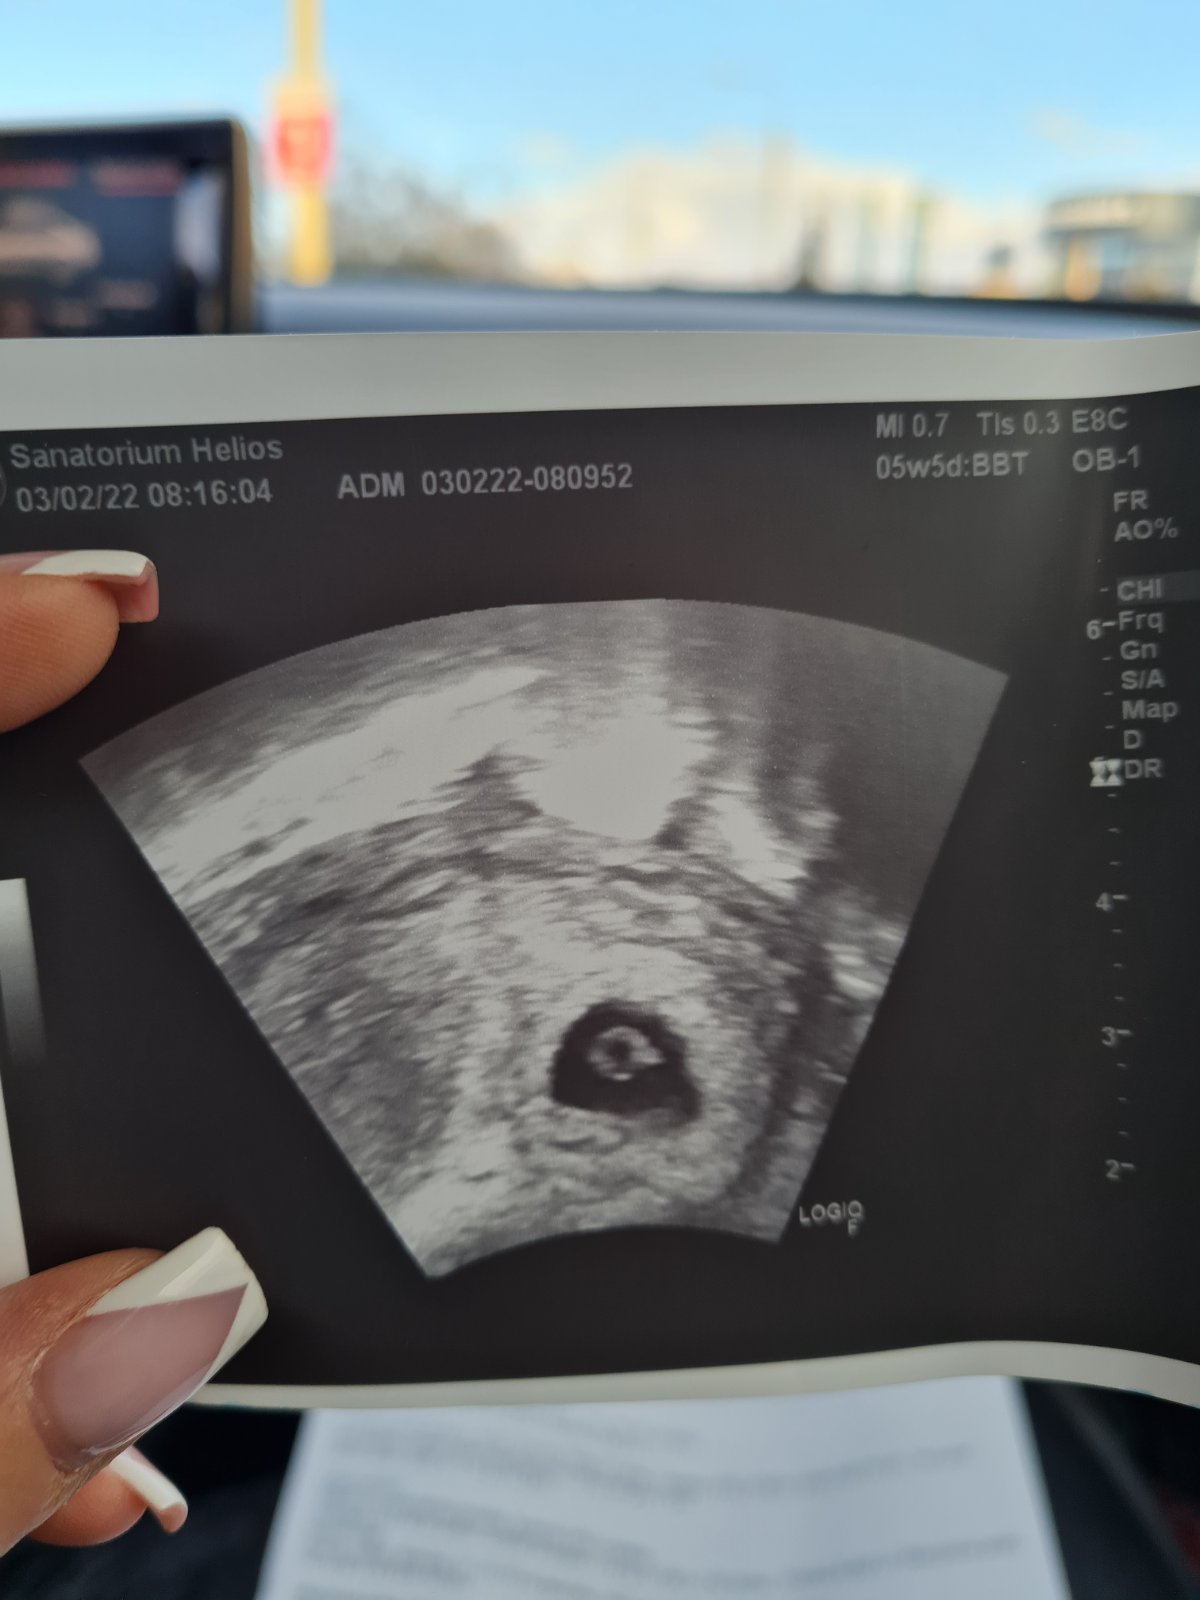

@lienka_9 ja som mala vklad 14.01.22 bola som na ultrazvuku minulý štvrtok a bolo vidno všetko okrem srdiečka... bola som podla MS v 5+5tt a podla ultrazvuku 6+1tt babatko vobec nezaostava prave naopak uz ho bolo vidieť malo 0.38 mm a čakáme na akciu srdiečka...ďalší ultrazvuk je 11.02.22 ❤❤❤